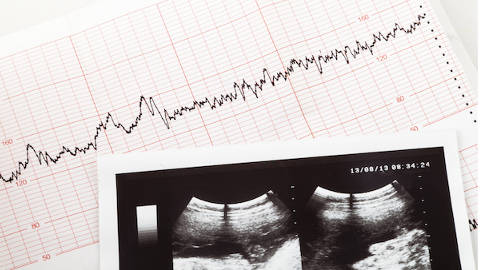

Week 5 is the earliest week that you might be able to hear your baby’s heartbeat during a transvaginal ultrasound. Because it it still so tiny, a fetal doppler device can’t pick up the heartbeat just yet.

If the heartbeat can’t be detected yet, don’t feel down! Remember that week 5 is the earliest time that the heart starts beating, but it doesn’t mean that it won’t develop in the next week or two. If a fetal pole can’t be visualized yet, a repeat ultrasound is performed in one or two weeks.